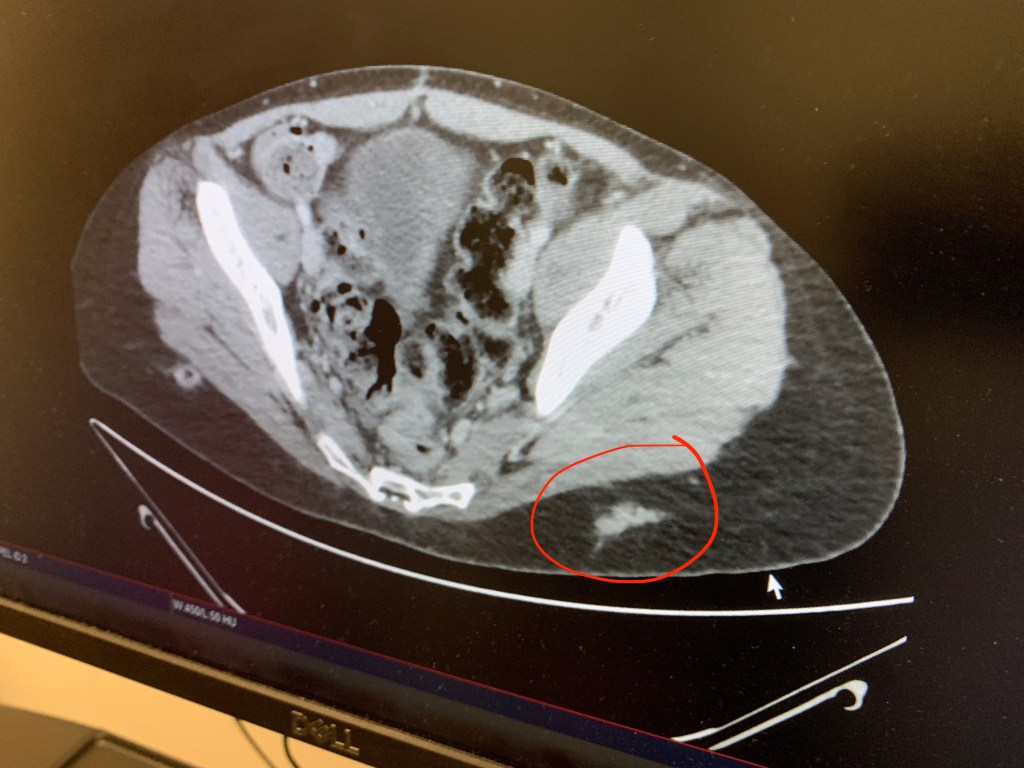

PS – On this CT Dr. Pommier discovered that the nurses have been poking me in the wrong spot for my Sandostatin shots!! They are poking me too far out toward my hips; the poke needs to be closer to my spine so the needle goes into my muscle. The CT clearly shows this, and I took a picture so I can show my nurses in the future (see below). As much as I have enormous respect and gratitude toward all the nurses that administer my shots, honestly at this point I probably know more about NETs and Sandostatin than most of them. Twice in the last year it wasn’t prepared correctly, and I was left with giant bruises. A reminder to advocate for myself!

You can see circled in red where my Sandostatin shots have been going into my fat instead of into my muscle.